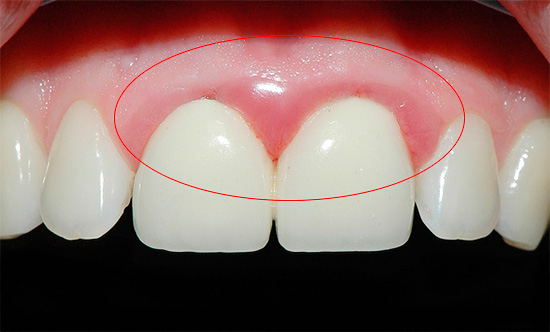

Há situações em que uma gengiva começa a doer sob uma coroa, não um dente. Uma coroa fixada em um dente pode passar excessivamente sob a gengiva com sua borda ou, inversamente, pode não atingir significativamente sua borda.

Na primeira opção, um trauma permanente com uma aresta aguda forma uma inflamação local, e a inflamação é acompanhada de dor, que "dá" ao dente. Como resultado, parece à pessoa que é o dente que dói sob a coroa, embora a causa esteja nas gengivas.

A foto abaixo mostra um exemplo de inflamação das gengivas em contato com as coroas:

Na segunda opção (quando a coroa não atinge as gengivas), geralmente a dor não ocorre logo. Atrasos freqüentes de comida entre a gengiva e a borda da coroa podem causar a mesma inflamação e dor no futuro como no primeiro caso, mas a cárie dentária provavelmente se desenvolverá, levando à destruição gradual dos tecidos duros sob a coroa com o aparecimento de uma reação dolorosa a calor, frio, pressão e pressão. outros irritantes.